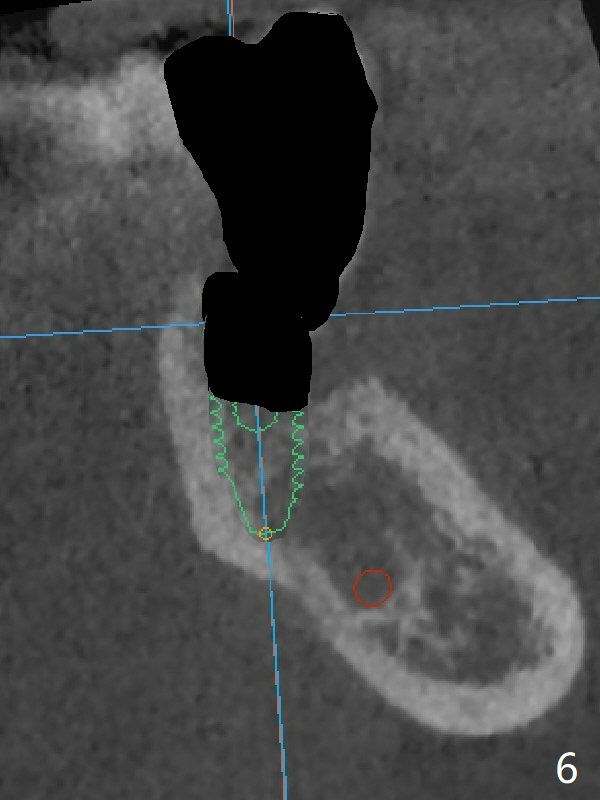

In contrast without implantation after extraction (Fig.6 (ignore green)), the socket may be grafted (Fig.7 pink circles) and covered by PRF membrane (red line). Due to the large socket with severe buccal defect, the graft is more likely to be lost (Fig.8). Several months later, an implant to be placed (Fig.9 green) will be short with unfavorable crown/implant ratio.